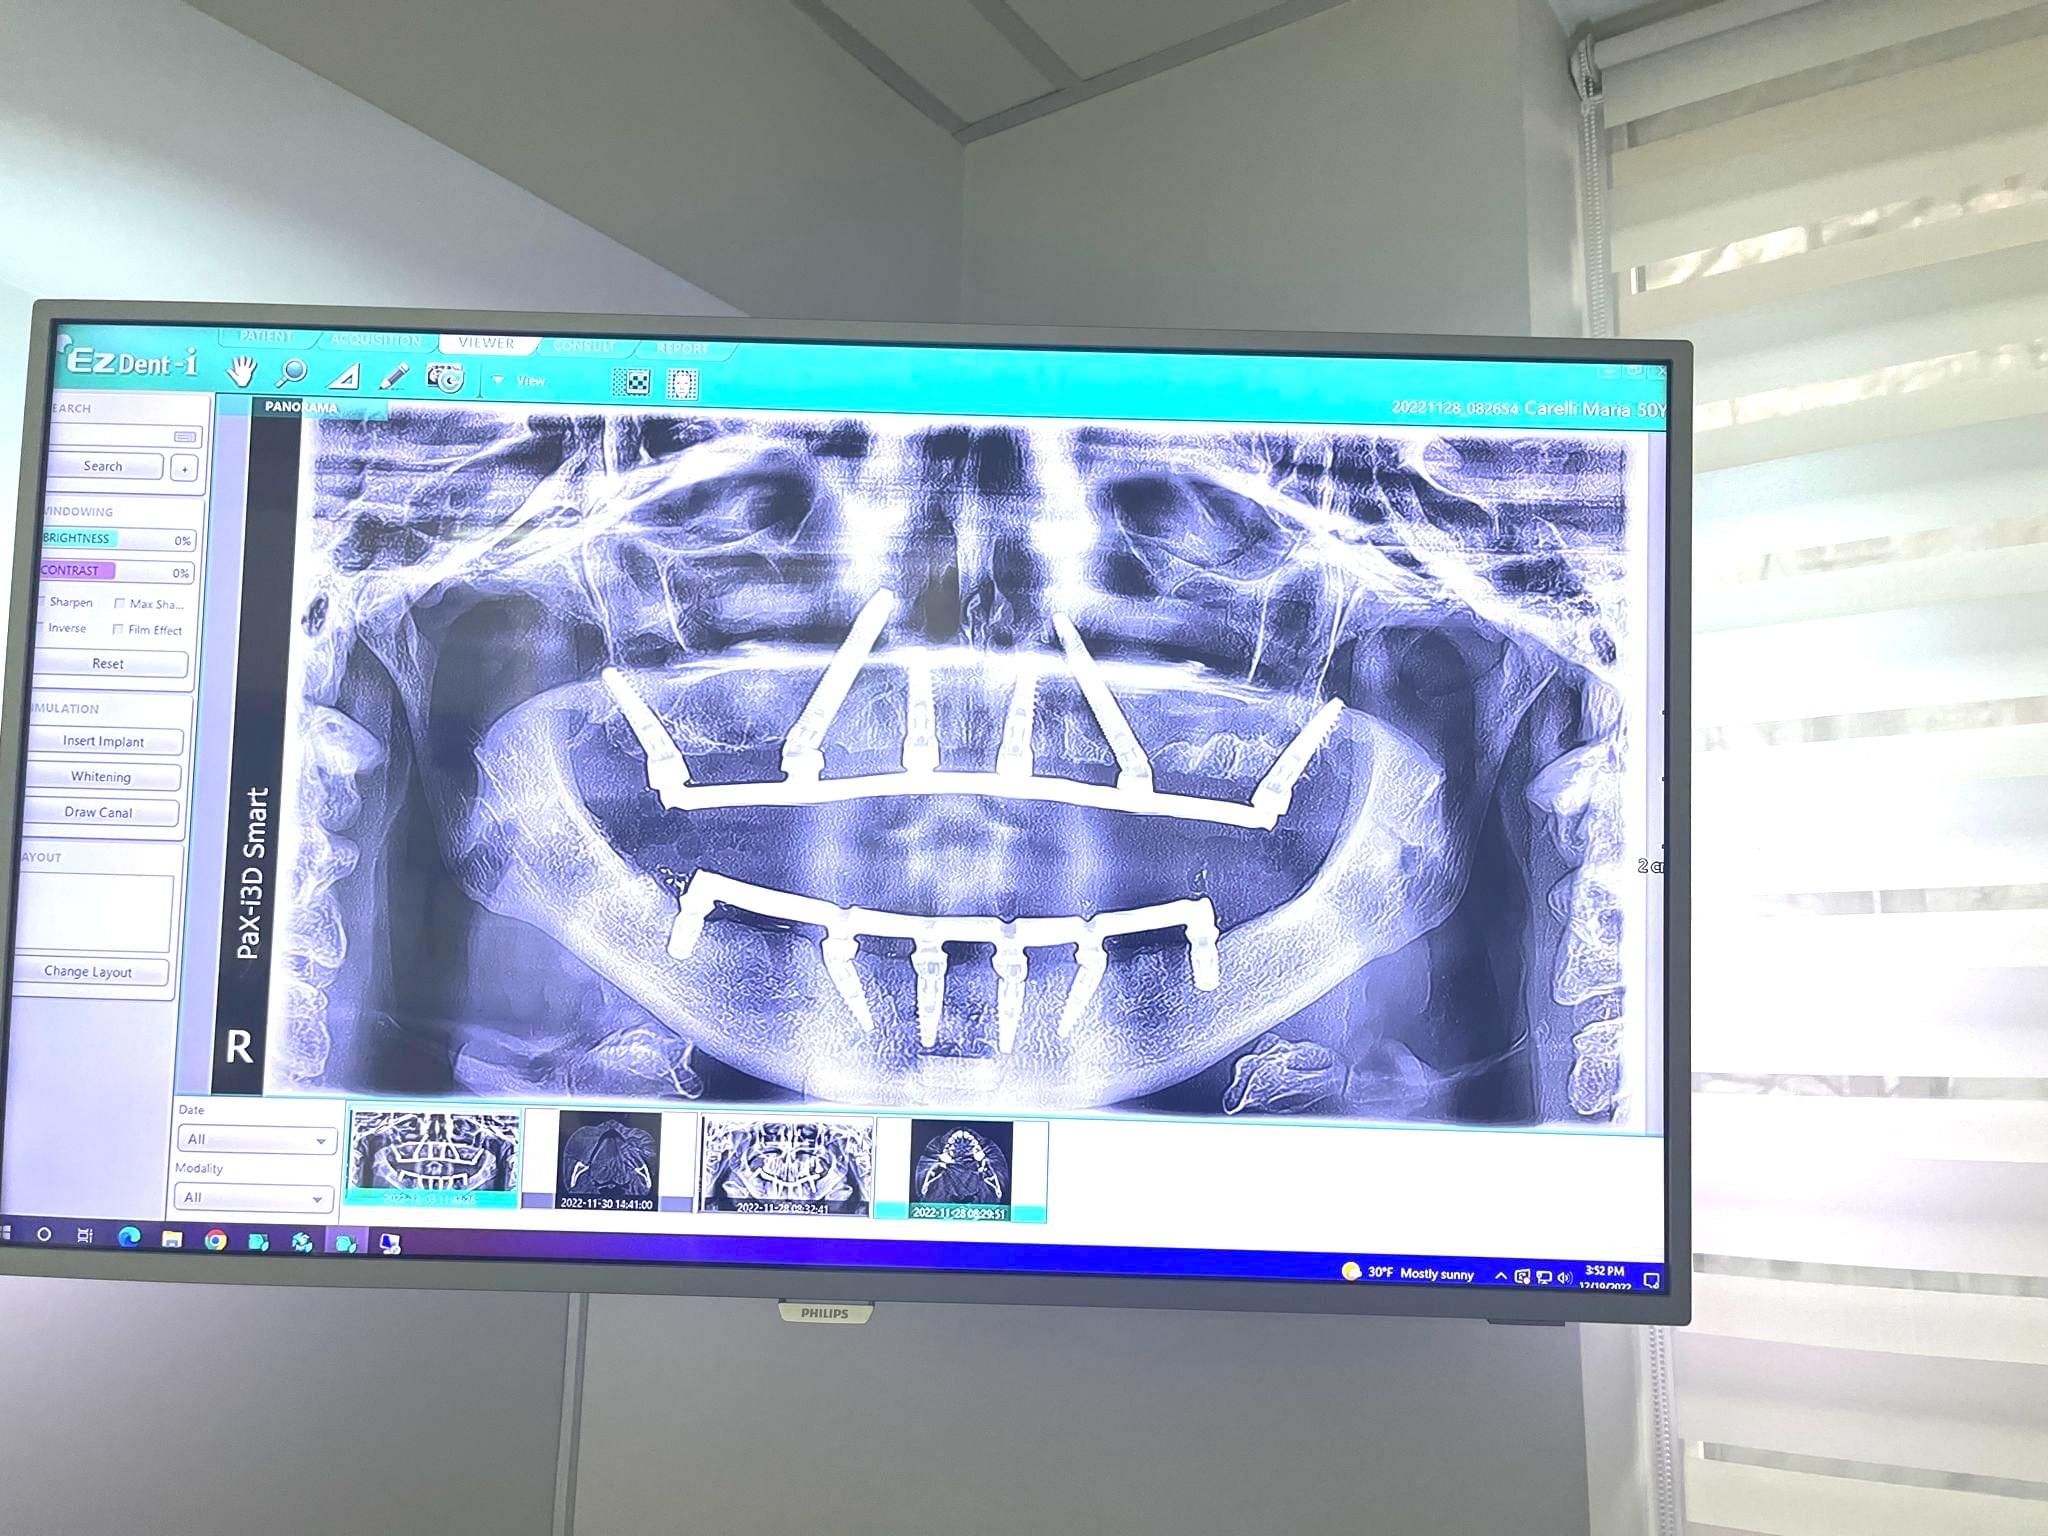

Ogni intervento chirurgico eseguito dall'Equipe del Dr Palmas viene pianificata partendo dalla TAC 3D del paziente.

Prima di decidere quale intervento chirurgico eseguire, vengono incrociati una serie di dati.

1. Dimensioni del viso

2. Denti residui in bocca

3. Desideri ed obiettivi del paziente

4. Budget del paziente

5. Numero di viaggi che occorreranno per ultimare il caso

6. Aspettativa di vita del paziente